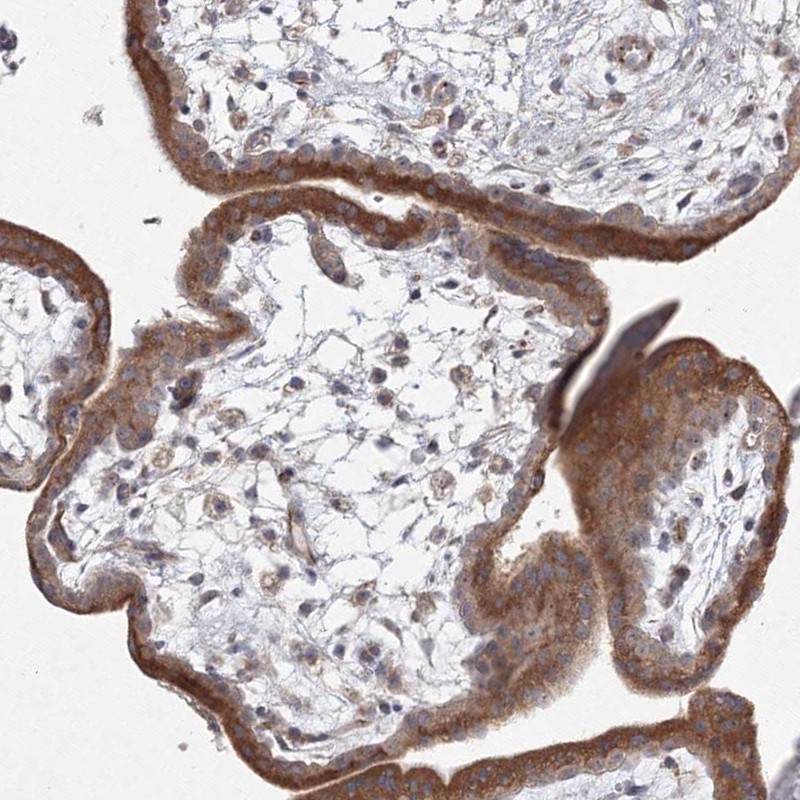

Immunohistochemical staining of human placenta shows strong cytoplasmic positivity in trophoblastic cells.